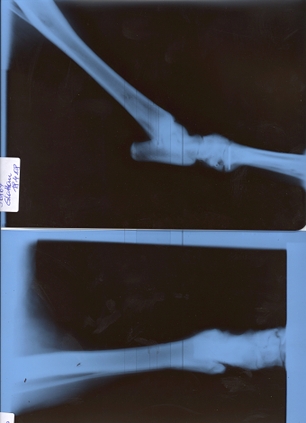

Mitte April 2008 waren wir bei Prof.Dr. Kopf in der Kleintierklinik Breitensse zur Nachkontrolle und die Röntgenbilder zeigen es: Alles in Ordnung!

Nochmal ein herzliches Danke an Dr. Kopf und sein Team, Sam läuft herum und wandert auch tagelang, als ob nie etwas gewesen wäre ...!